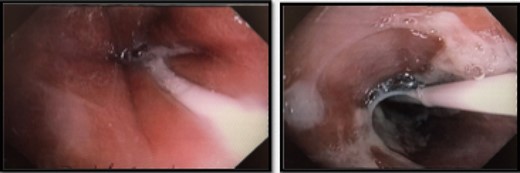

He was commenced on high-dose PPI, IV Antibiotics and analgesia. Emergency gastroscopy showed middle third of esophagus consistent with esophagitis and circumferential ischemia/necrosis in distal esophagus 27–34 cm (Fig. 6). Mucosal biopsies taken revealed ulcerated squamocolumnar mucosa with necrosis and inflammation. No CMV inclusions were identified.